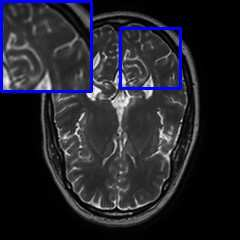

Limited by imaging systems, the reconstruction of Magnetic Resonance Imaging (MRI) images from partial measurement is essential to medical imaging research. Benefiting from the diverse and complementary information of multi-contrast MR images in different imaging modalities, multi-contrast Super-Resolution (SR) reconstruction is promising to yield SR images with higher quality. In the medical scenario, to fully visualize the lesion, radiologists are accustomed to zooming the MR images at arbitrary scales rather than using a fixed scale, as used by most MRI SR methods. In addition, existing multi-contrast MRI SR methods often require a fixed resolution for the reference image, which makes acquiring reference images difficult and imposes limitations on arbitrary scale SR tasks. To address these issues, we proposed an implicit neural representations based dual-arbitrary multi-contrast MRI super-resolution method, called Dual-ArbNet. First, we decouple the resolution of the target and reference images by a feature encoder, enabling the network to input target and reference images at arbitrary scales. Then, an implicit fusion decoder fuses the multi-contrast features and uses an Implicit Decoding Function~(IDF) to obtain the final MRI SR results. Furthermore, we introduce a curriculum learning strategy to train our network, which improves the generalization and performance of our Dual-ArbNet. Extensive experiments in two public MRI datasets demonstrate that our method outperforms state-of-the-art approaches under different scale factors and has great potential in clinical practice.